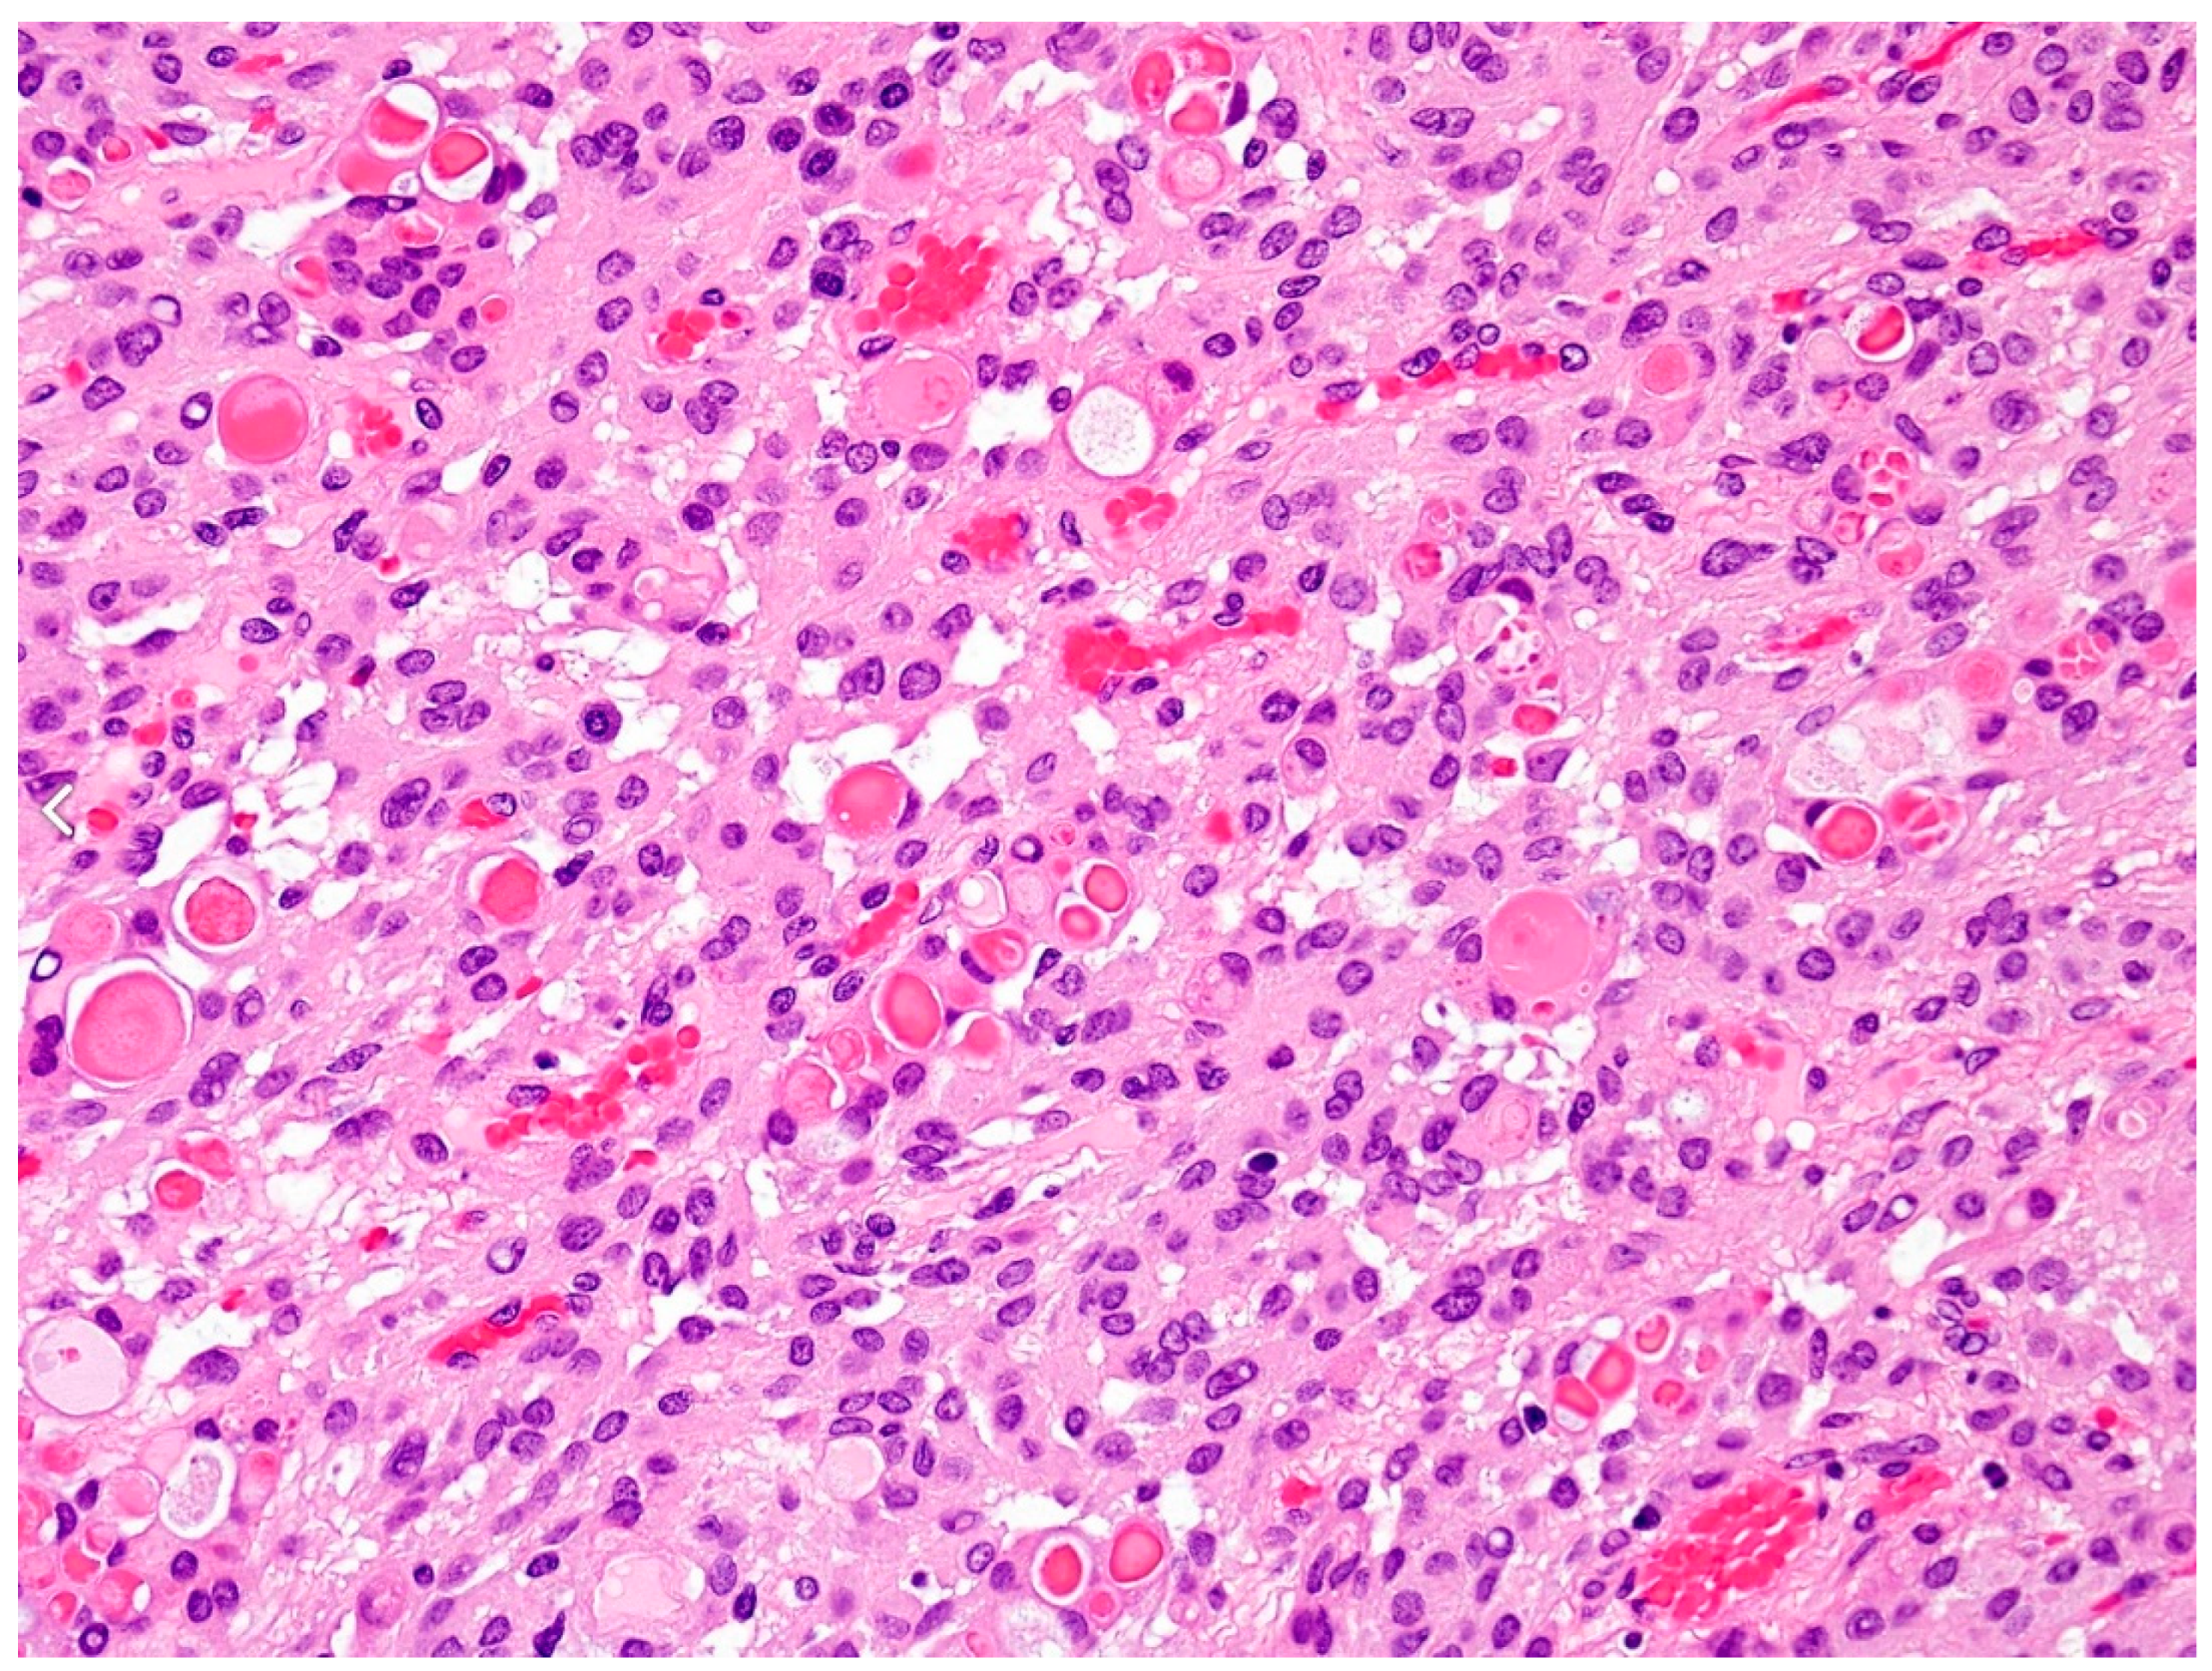

| Grade 2 (atypical-aggressive) | Mitotic rate 4–19 per 10 HPF or Brain invasion or ≥3 or 5 specific histologies: • Spontaneous or geographic necrosis; • Patternless sheet-like growth; • Prominent nucleoli; • High cellularity; • Small cells with high n:c ratio. |

| Grade 3 (anaplastic-aggressive and malignant) | Mitotic rate > 20 per 10 HPF (HPF: high-power field) or Specific histologies: papillary or rhabdoid (since WHO 2021 graded on the basis of the same criteria for atypia and anaplasia as for other meningioma variants). Since WHO 2021: frank anaplasia (melanoma-, sarcoma- or carcinoma-like histology) CDKN2A and/or CDKN2B homozygous deletion TERT promoter mutation |